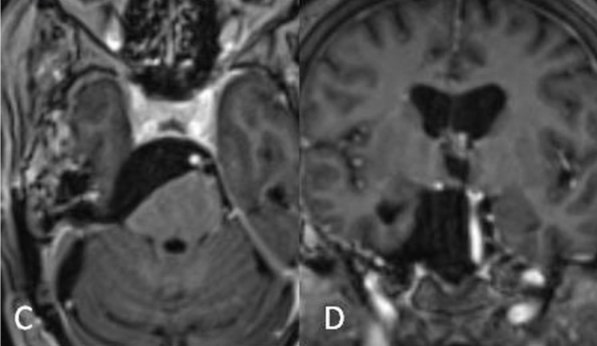

经过周密的术前准备,福教授手术团队为患者进行了颅内肿瘤切除术。采用mini-CTPA手术切除肿瘤。在脑干上附着残体进行NTR(图C,D)。无神经功能缺损。

术后:C术后轴位和D位冠状位磁共振增强图像显示肿瘤大体切除,神经血管结构合适减压